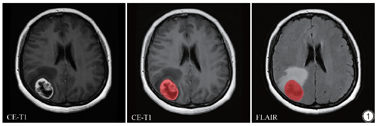

首先将T2-FLAIR图像通过FSL软件(http://fsl.fMRIb.ox.ac.uk/fsl/fslwiki/FSL)采用仿射变换与相应的CE-T1图像进行配准。肿瘤感兴趣区(region of interest, ROI)的勾画利用ITK-SNAP软件(http://www.itksnap.org)进行。由两名年资在10年以上的放射科主治医生进行双盲手动勾画,重叠区作为肿瘤的感兴趣区。并最终由一名年资超过20年的放射科主任医生审验。在CE-T1 MRI的图像上勾画出ROI,然后配准到T2-FLAIR图像上(图1)。